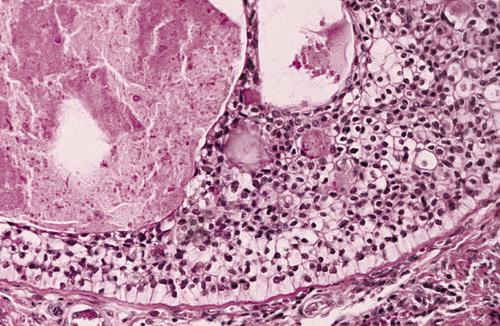

Histopathologic Features

- loosely arranged fibrous connective tissue wall

- islands or cords of odontogenic epithelial rests

- two to four layers of flattened nonkeratinizing cells

- focal areas of mucous cells in epithelial lining

This noninflamed cyst shows a thin, nonkeratinized epithelial lining and a loosely arranged fibrous connective tissue wall.

dentigerous cyst, noninflamed

This inflamed cyst shows a thick epithelial lining with hyperplastic rete ridges and diffuse chronic inflammatory infiltrate.

dentigerous cyst, inflammed

This cyst shows scattered mucous cells within the thin epithelial nonkeratinized epithelial lining.

dentigerous cyst